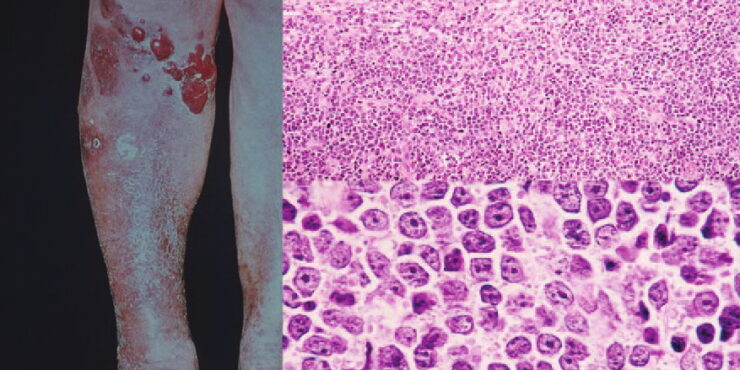

Diffuse large B-cell lymphoma = اللمفوما كبيرة الخلايا البائية المنتشرة